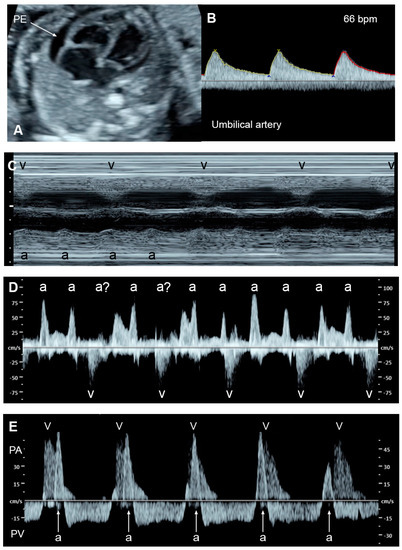

| Normal | −1 Point | −2 Points | |

|---|---|---|---|

| Hydropic signs | Absence of effusion | Abdominal or pleural, or pericardial effusion | Skin edema |

| Venous Doppler (umbilical vein: UV & ductus venosus: DV | Normal Doppler UV ![]() DV ![]() | Reversed ductus venosus flow UV ![]() DV ![]() | Pulsatile flow in the umbilical vein UV ![]() |

| Heart size (Cardio-thoracic ratio) | ≤35% | 35–50% | >50% or <20% |

| Cardiac function | Normal function | Holosystolic TR, or ventricular shortening fraction < 28% | Holosystolic MR or TR dP/dt < 400, or monophasic inflow |

| Arterial Doppler (umbilical artery) | Normal Doppler![]() | Absent end-diastolic flow![]() | Reversed end-diastolic flow![]() |